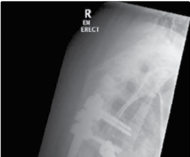

The foundation of successful thoracolumbar surgery lies in exhaustive preoperative planning. Standard imaging protocols must include full-length, free-standing 36-inch orthogonal radiographs to accurately assess global coronal and sagittal balance. The use of EOS low-dose biplanar imaging has become the gold standard, allowing for simultaneous assessment of the spine, pelvis, and lower extremities, which is crucial for identifying compensatory mechanisms such as pelvic retroversion, hip extension, and knee flexion. Magnetic Resonance Imaging (MRI) is mandatory to evaluate the neural elements, assess disc hydration, and identify central, lateral recess, or foraminal stenosis.

High-resolution computed tomography (CT) with multiplanar reconstruction is essential for evaluating bone stock, identifying facet arthropathy, and planning pedicle screw trajectories. In cases of severe deformity or revision surgery, CT-based 3D templating software allows the surgeon to simulate osteotomies, calculate the exact degree of correction required to achieve spinopelvic harmony, and pre-contour rods. The surgeon must meticulously calculate the required Lumbar Lordosis (LL) based on the patient's Pelvic Incidence (PI), plan the upper and lower instrumented vertebrae (UIV and LIV) to avoid ending the construct at the apex of a kyphotic curve, and determine the necessity of pelvic fixation.

Clinical & Radiographic Imaging Archive